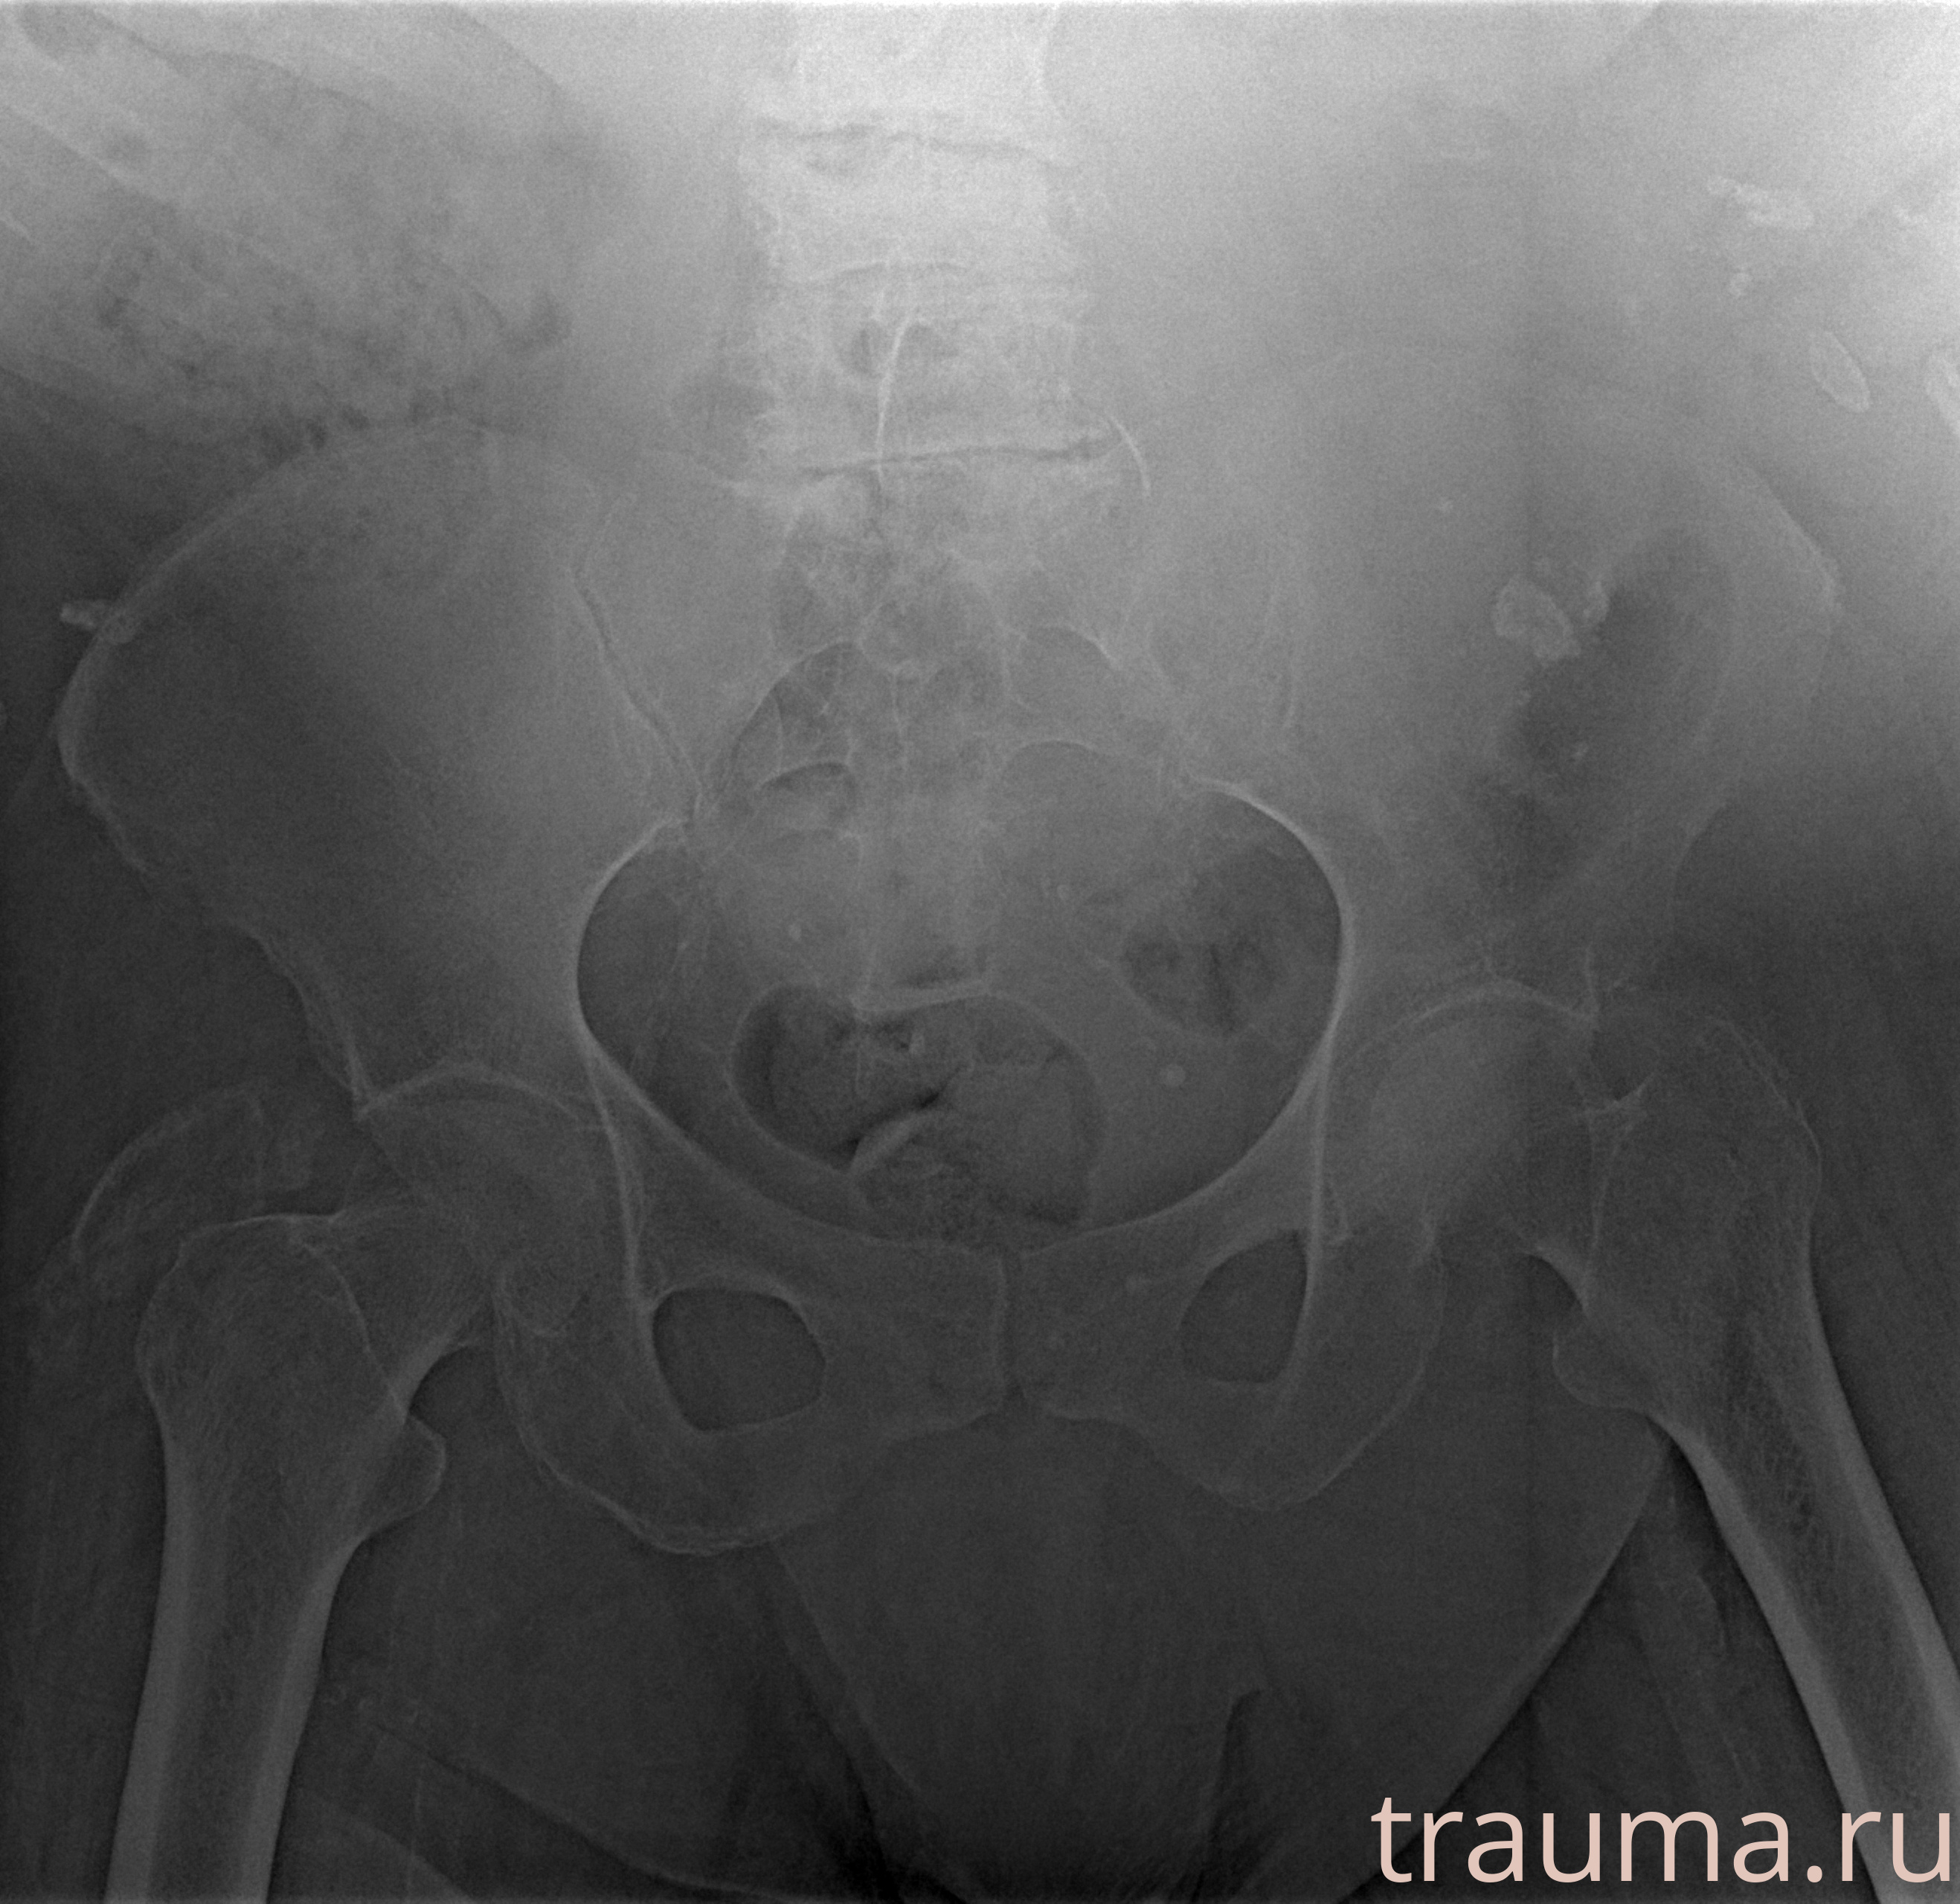

Рентгенограммы

Рентген на дому: по вашему адресу приезжает врач-рентгенолог, травматолог-ортопед с мобильным рентгеновским аппаратом, проводит диагностику травмы или заболевания, делает необходимые рентгенограммы, дает рекомендации по дальнейшему лечению. Получить качественные снимки в домашних условиях возможно благодаря уникальной методике, разработанной МосРентген Центром для института  Склифосовского